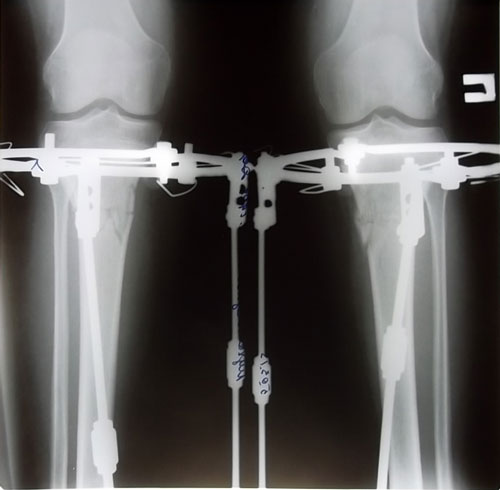

Основные крутки закончены.

Сегодня день прошел не заметно. Приходил Константин Николаевич. Я ходила на рентген. Приходила секретарь делала снимки ножек. Много ходила что левая нога каждый раз затекала. Приходилось периодически ложиться и поднимать ноги. А так хотелось больше ходить и ходить. Тем более что тут новенькие охото поболтать с ними. Сегодня приехала еще одна девочка на ОП. Очень рада за них они все по акции делают. Повезло им. Я сегодня впервые ходила на кастылях и спускалась на них по ступенькам. Такая довольная. И сегодня я очень устала.